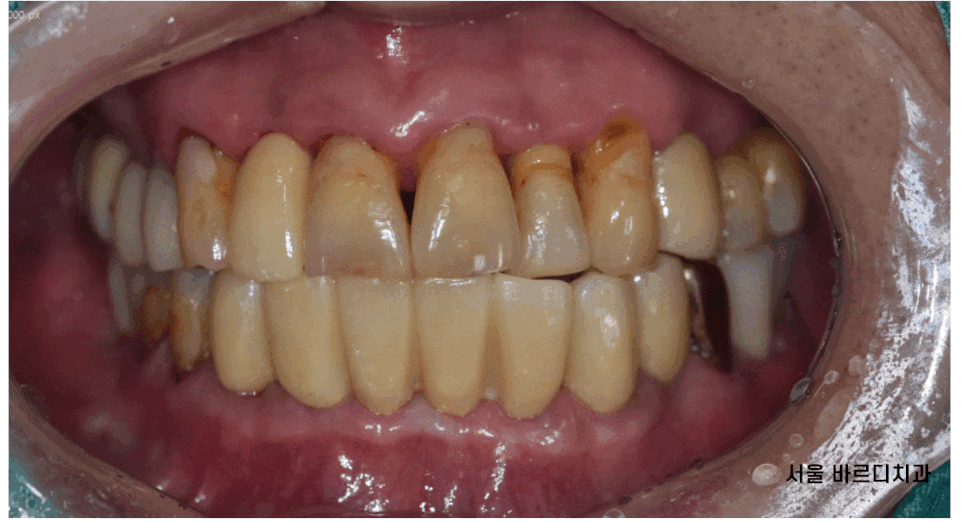

오늘 환자분도 전반적으로 치아가 흔들거려서

내원해주신 환자분입니다.

잇몸이 염증이 있고

흔들려요

위아래로 쎄게 물었을 때

통증까지 느껴지신다고 하셨습니다.